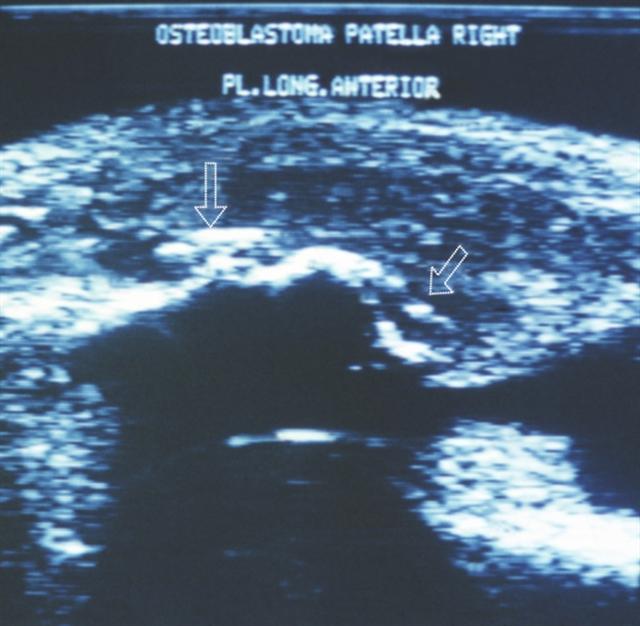

Рис. 23. Ультрасонограмма правого коленного сустава (передний продольный срез) при остеобластокластоме надколенника: контур надколенника неровный, в мягких тканях определяются несколько фокусов повышенной эхогенности (указаны стрелками).